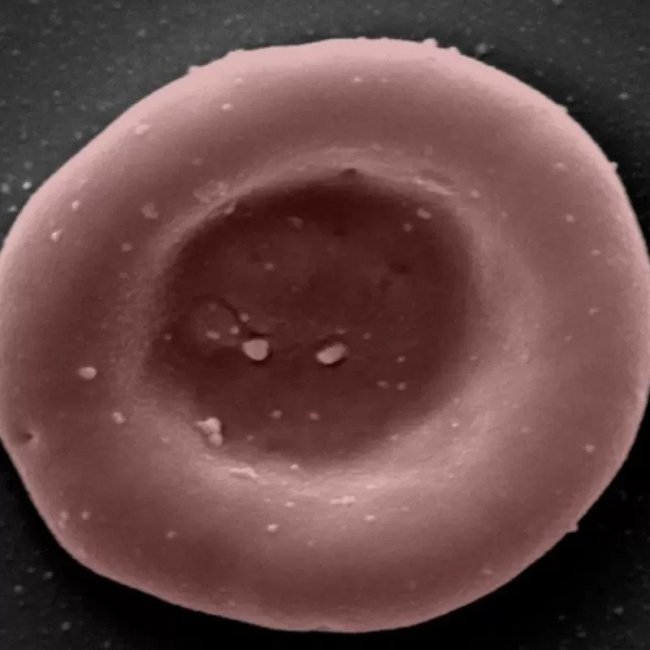

Bristol Üniversitesi’nden Profesör Ashley Toye, bazı kan gruplarının çok nadir olduğunu söylüyor ve "sadece 10 kişide görülen" kan gruplarının var olduğunu anlatıyor. Örneğin ilk kez Hindistan’da görülen Bombay adı verilen kan grubundan İngiltere çapında yalnızca üç ünite bulunuyor. Bu araştırma projesi Bristol Cambridge, Londra’da ekiplerin birlikte çalışması ile ilerliyor ve ciğerlerden vücuda oksijen taşıyan kırmızı kan hücrelerine odaklanıyor.